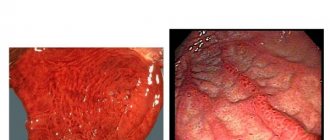

Acute cholecystitis

Inflammation of the mucous membrane occurs when infectious agents enter it (hematogenously or lymphogenously), which most often are Escherichia coli or staphylococci.

Concomitant cholelithiasis and structural anomalies contribute to the occurrence of cholecystitis. Young patients with acute inflammation complain of: